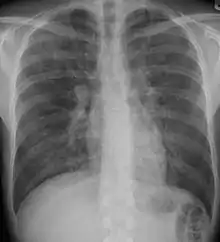

Chest radiography is usually the first test to detect interstitial lung diseases, but the chest radiograph can be normal in up to 10% of patients, especially early in the disease process.[13][14]

High-resolution CT of the chest is the preferred modality and differs from routine CT of the chest. Conventional (regular) CT chest examines 7–10 mm slices obtained at 10 mm intervals; high resolution CT examines 1–1.5 mm slices at 10 mm intervals using a high-spatial-frequency reconstruction algorithm. The HRCT therefore provides approximately 10 times more resolution than the conventional CT chest, allowing the HRCT to elicit details that cannot otherwise be visualized.[13][15]

Radiologic appearance alone, however, is not adequate and should be interpreted in the clinical context, keeping in mind the temporal profile of the disease process.[13]